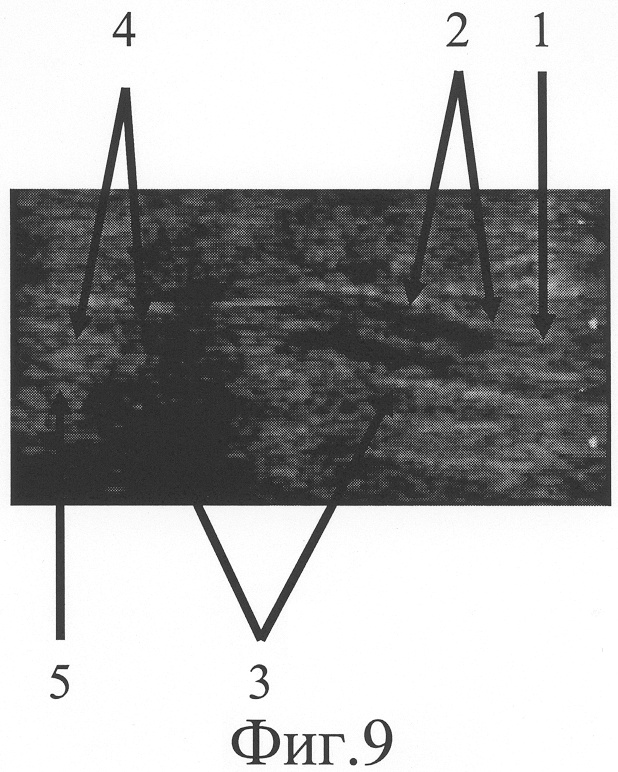

На фиг.9 представлена сонограмма больного П., 51 года, с застарелым повреждением локтевого нерва в средней трети правого предплечья (через 5 недель после начала дистракции).

Через 5 недель после начала дистракции на сонограмме (фиг.9) на месте дефекта выявлен регенерат локтевого нерва (фиг.9-1), заканчивающийся невромой, линейный размер которой составляет 4 мм (фиг.9-2), его дистальный фрагмент с патологическими изменениями на протяжении 5 мм (фиг.9-5). Диастаз между невромой и дистальным фрагментом стал равен 15 мм (фиг.9-5). Размер участка локтевого нерва, подлежащего возмещению, сократился до 24 мм. Дозированная дистракция на шине продолжалась.